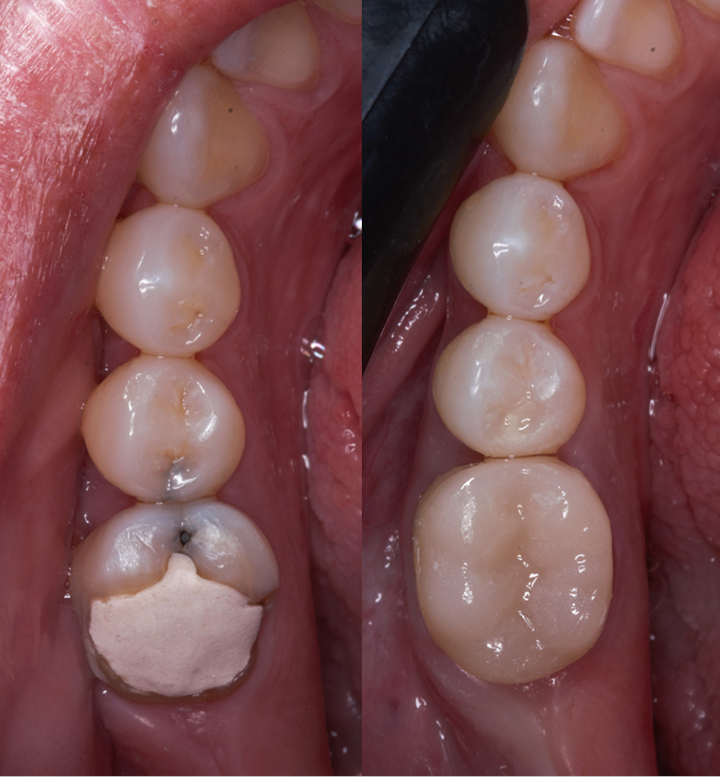

Em dentes com uma grande destruição e cuja resistência se encontra reduzida está indicado o tratamento com restaurações em cerâmica (overlay/coroa). Estes tipos de restaurações são confecionadas em laboratório e permitem reforçar a estrutura do dente, permitindo uma maior longevidade do mesmo.